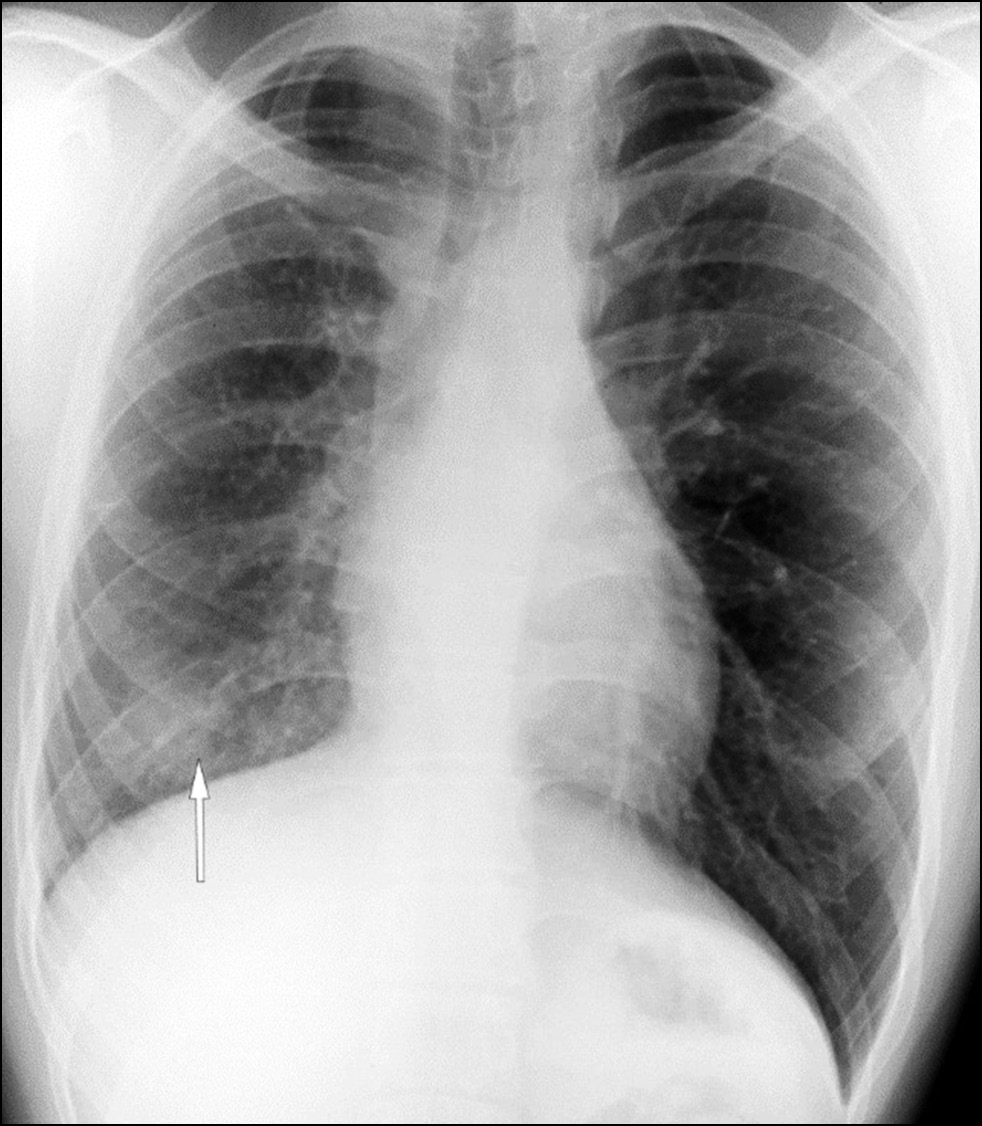

Diagnosis of thoracic aortic aneurysms and pathological pulmonary trunk dilation using chest computed tomography and artificial intelligence: modern approaches and prospects (a review)

Abstract

Early diagnosis of thoracic aortic aneurysms and pathological pulmonary trunk dilation is crucial to prevent severe complications, including vascular wall rupture and acute right ventricular failure, and reduce cardiovascular mortality. This review examines contemporary imaging approaches for these conditions, focusing on computed tomography as the gold standard modality. Emphasis was placed on the implementation of artificial intelligence technologies, which enable automatic segmentation of vascular structures, measurement of their diameter, and opportunistic screening, allowing early detection of asymptomatic conditions without additional diagnostic procedures, thereby reducing radiologist workload and improving medical care quality. The study comprehensively analyzed the Moscow Experiment, wherein the application of artificial intelligence in medical image analysis showed high sensitivity, reproducibility, and reduced reporting time. Despite these significant advantages, the need for expert supervision of artificial intelligence-generated results to ensure diagnostic accuracy and reliability is emphasized. Moreover, the review highlights the importance of adapting algorithms to different scanning protocols and population-specific features. Additionally, the importance of interdisciplinary collaboration among cardiologists, radiologists, data scientists, and software developers for the effective integration into routine clinical practice is pointed out. Therefore, the review outlines the potential of artificial intelligence technologies to enhance diagnostic quality and underscores the need for further clinical research and standardization of methods for successful integration into daily practice.